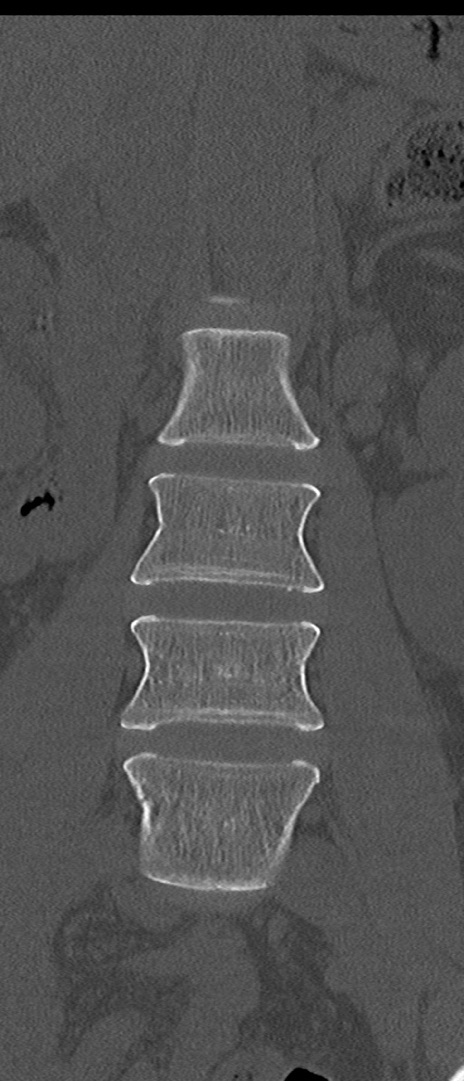

【整形】TIPS症例4 腰椎CT(冠状断像)

腰椎CT

矢状断像